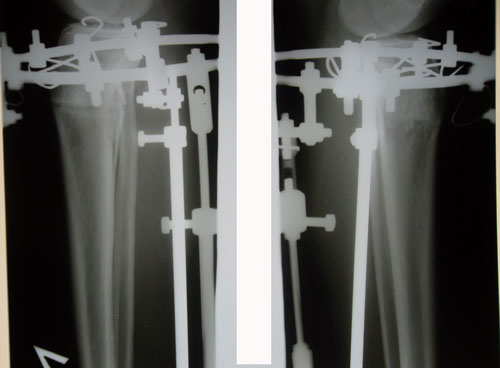

Рентген в 2,5 месяца с момента операции.

SAM_7267.JPG

SAM_7266.JPG